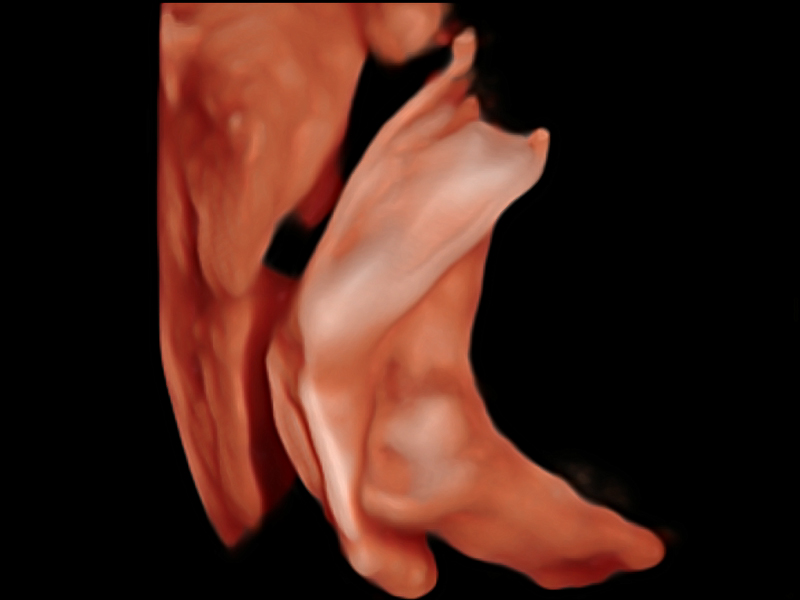

• 产科扫查助手S-Fetus

S-Fetus基于大数据深度学习算法,能够帮助您在产前筛查过程中智能识别胎儿标准切面、自动测量并录入报告。一个按键,即可智能、精准、高效地获取胎儿生理指标,极大简化您的产科检查操作。